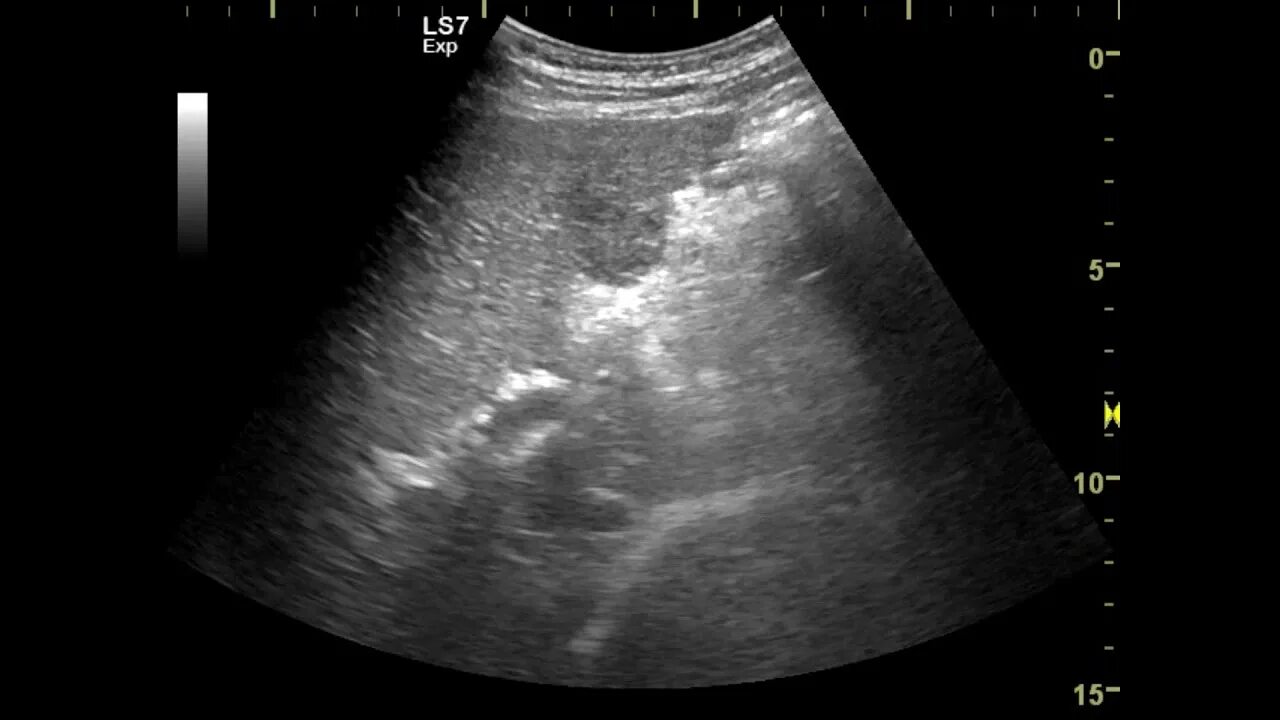

3 метастазы в печени